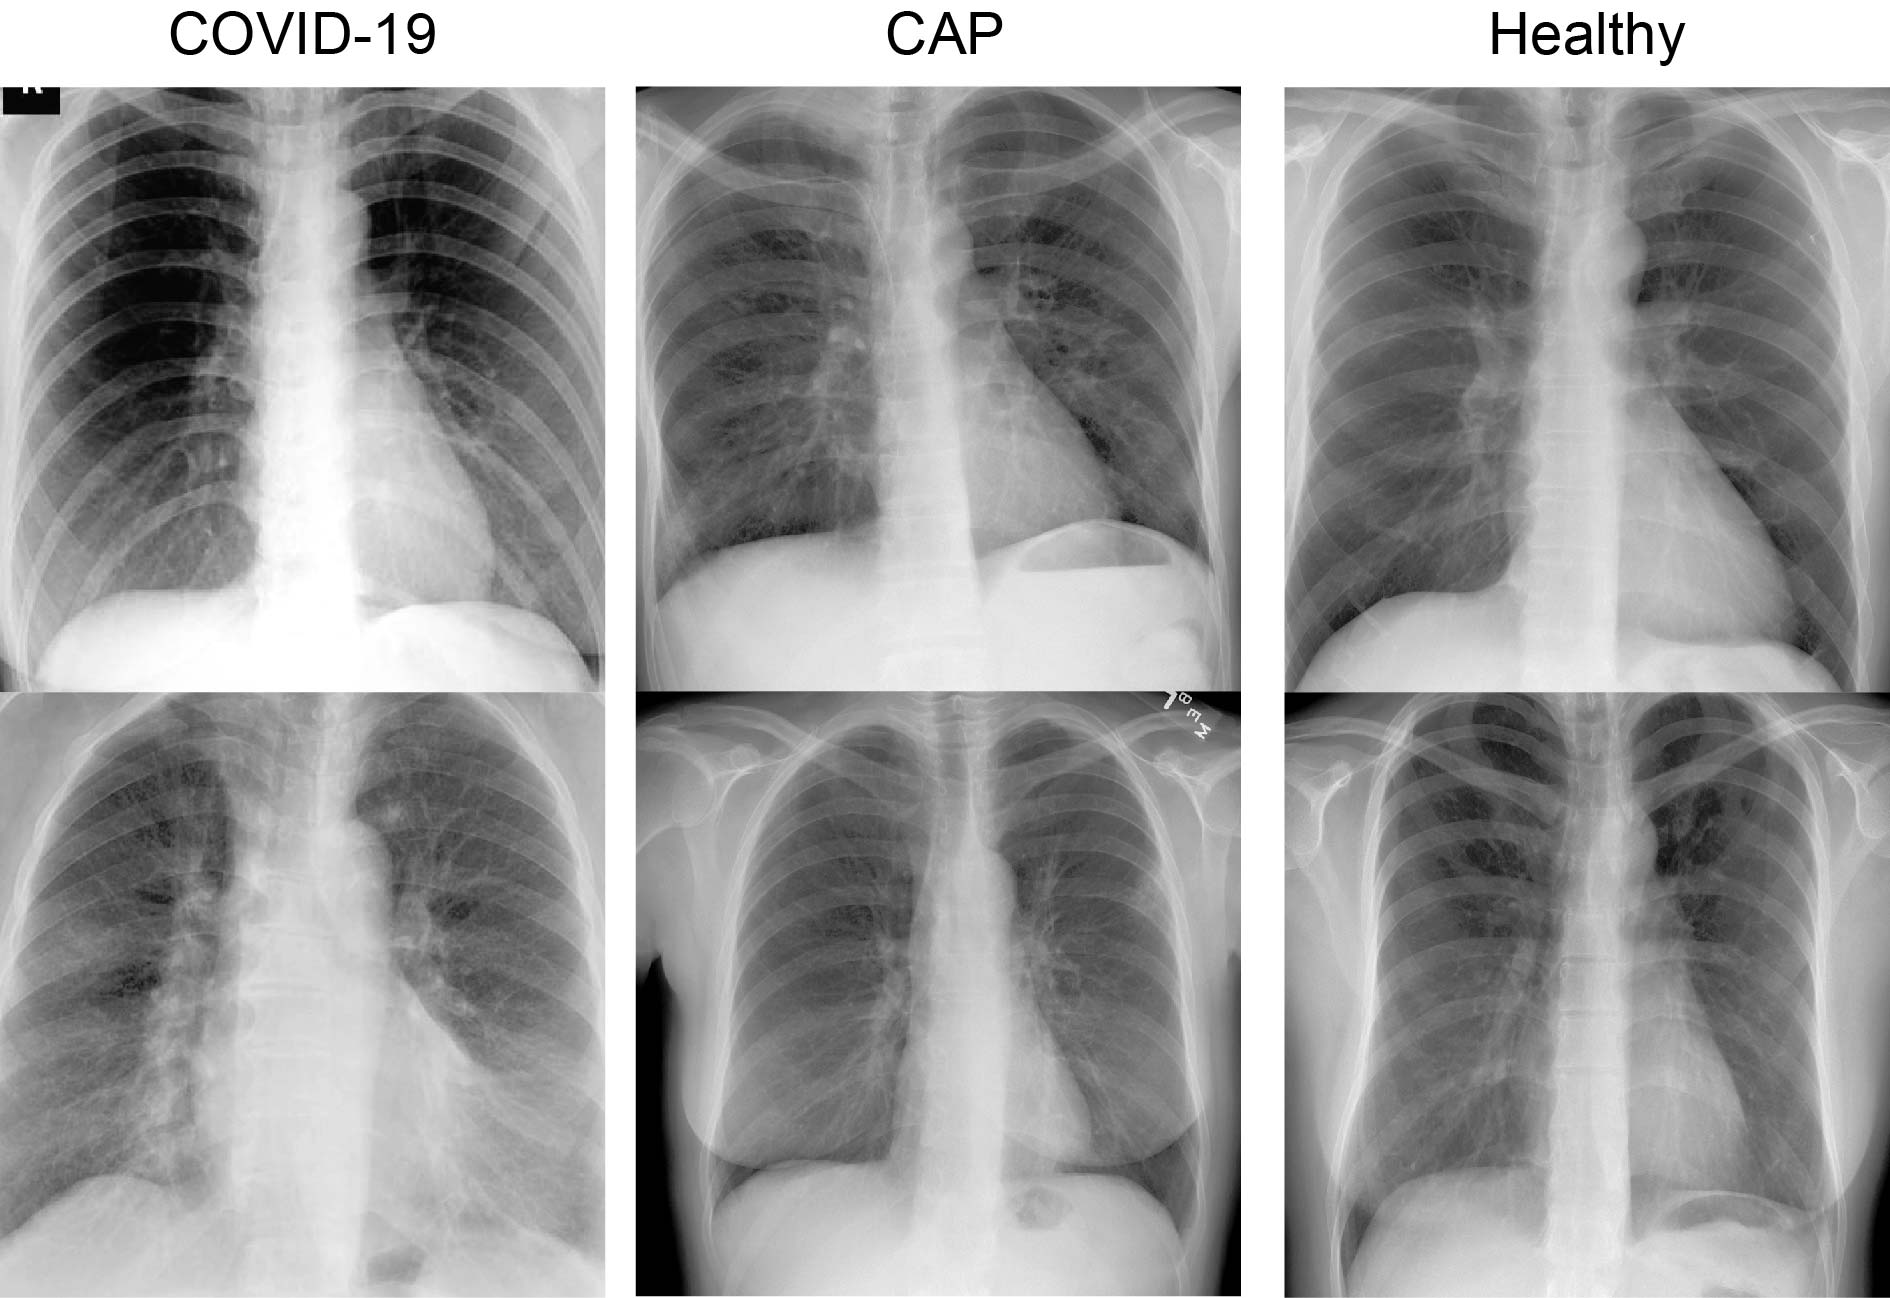

Since COVID-19 datasets are becoming more abundant, existing sets are constantly growing and evolving, and it has become important to cite the data source and the day it was acquired. Specifically, this study uses data from the Cohen et al. [4] chest x-ray dataset that was acquired on 2020-04-17. This dataset contains three classes: 1) healthy, 2) community acquired pneumonia (CAP), and 3) COVID-19 (examples in Figure 1). We employed a modified 80-10-10 TVTS (Table I) training paradigm. It was modified to maximize the number of COVID-19 training samples and double the size of the test hold out set used in previous work [5]. The dataset version at the time of this study was large enough to accommodate the addition of a COVID-19 validation set and test hold out set 2x larger than previous work (from 10 hold out images to 20) [5].

Refer to caption

Figure 1: Two example images from each class in the dataset.